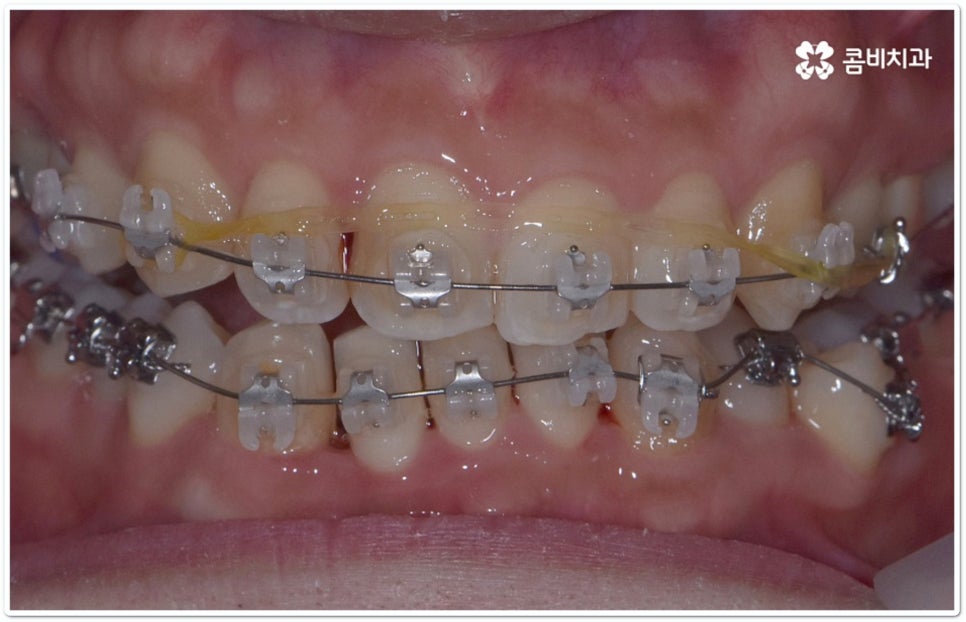

클리피씨교정 장치란 clippy-c 라는 단어 뜻에서 알 수 있듯이 클립이 달린 (clippy) 세라믹(ceramic) 브라켓 장치를 의미하고 있어요. 예전에 교정 장치에서 많이 쓰이던 방식은 고무줄 또는 미세철사를 이용하여 브라켓마다 각각 와이어를 묶어주는 것으로 날카롭게 잘린 철사 끝부분에 자칫 상처를 입을 수도 있고 한 달에 한 번 정도 치과에 내원하여 진행 상황에 따라 교정력을 조정하는 시간도 훨씬 더 많이 걸렸다고 할 수 있습니다.

이와는 다르게 클리피씨교정 장치는 자가결찰방식이라고 해서 각 브라켓에 여닫을 수 있는 특수한 클립(뚜껑)이 달려 있어 전체 와이어를 통과시켜 잡아주는 방식을 이용하기 때문에 겉면이 매끄럽고 진료 시간도 짧아지며 마찰로 빠져나가는 교정력을 줄여주어 좀 더 효율적으로 치아를 이동시킨다고 할 수 있어요. 즉 보다 적은 힘으로 지속적이고 부드러운 치아 이동을 가능하게 하므로 언급했던 것처럼 개인차가 있지만 전체 기간을 약 6개월 정도 단축시키고 치아가 이동할 때 느낄 수 있는 초기 통증도 감소시켜 줄 수 있는 거예요. 또한 치아 색상과 비슷한 세라믹 재질을 이용하기 때문에 음식을 먹거나 대화를 하는 등 입을 벌렸을 때 보일 수 있는 교정 장치가 그렇게 크게 눈에 띄지 않아 심미적으로도 뛰어나다는 장점을 가지고 있습니다.